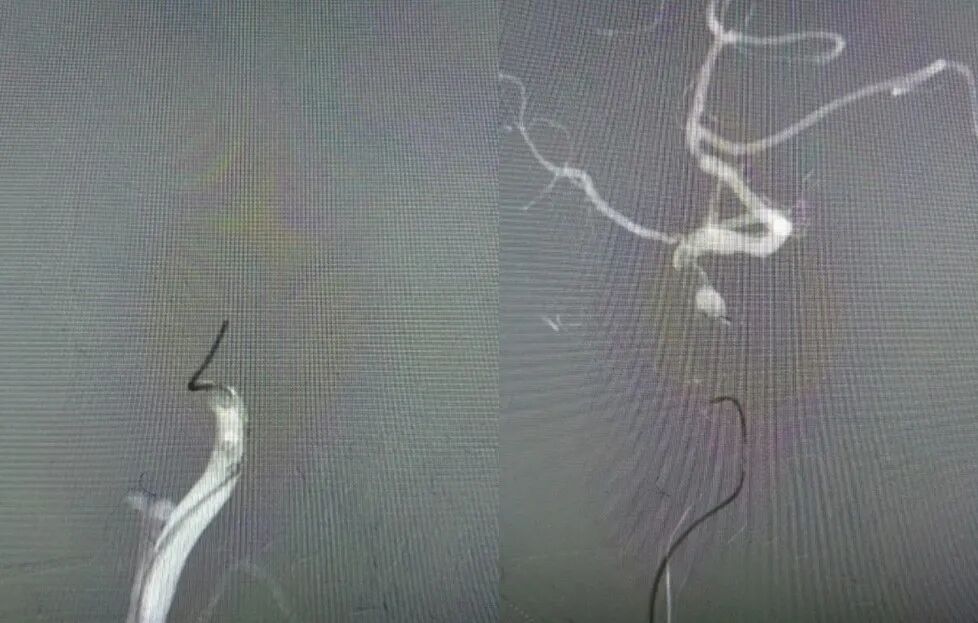

术后影像及检查

术后正位造影。

导丝怎么扩【载药时代 球扩天下】NOVA DES®颅内药物洗脱支架在大脑中动脉重度狭窄的应用二例!_https://www.jmylbn.com_新闻资讯_第30张

术后侧位造影

导丝怎么扩【载药时代 球扩天下】NOVA DES®颅内药物洗脱支架在大脑中动脉重度狭窄的应用二例!_https://www.jmylbn.com_新闻资讯_第31张